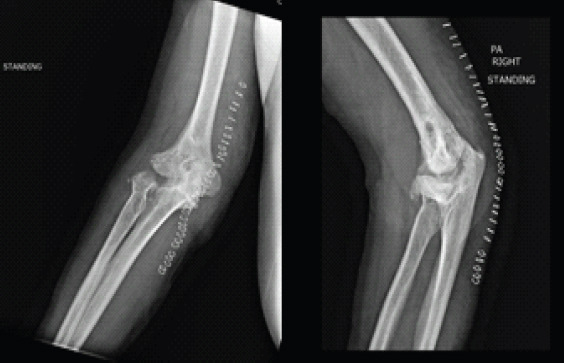

Case report: We report a case of a 50-year-old male who presented after the development of post-traumatic arthritis of the elbow after multiple prior surgeries. He was treated with an interpositional arthroplasty using an Achilles tendon graft and allowed immediate range of motion as tolerated in a hinged elbow brace without the use of any form of distraction external fixation. At his final follow-up, he has significantly improved pain, range of motion, and patient-reported Visual Analog Scale , American shoulder and elbow surgeons, mayo elbow performance score, and disabilities of the arm, shoulder and hand scores.